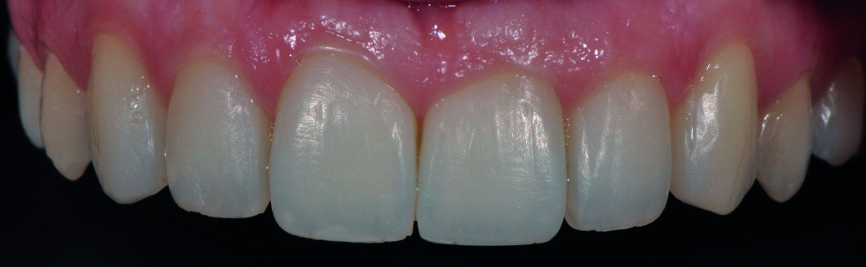

Fig. 3a : Le sourire après redéfinition de la forme des canines en incisives latérales avec le composite Essentia (GC).

Fig. 3b : Gros plan du sourire après redéfinition de la forme. Il a été possible d’obtenir un résultat très plaisant avec les restaurations composites en technique directe